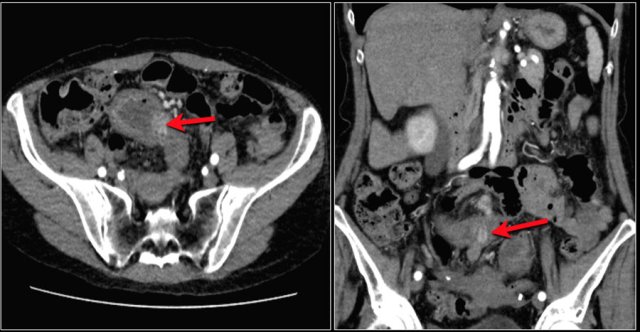

Here a patient with metastatic melanoma.

Left image shows ileal-ileal intussusception due to metastasis.

Right image shows intussusception in coronal plane as well as an enlarged mesenteric lymph node (yellow arrow) and extensive liver metastases.